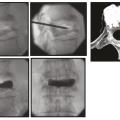

La vertébroplastie est une invention française.1 L’injection de ciment dans le corps vertébral par voie transcutanée « regonfle » le corps vertébral tassé et le rend solide et indolore (fig. 1 ). C’est le traitement minute de la fracture : lever immédiat sans corset et retour à une activité normale sans attendre.2 Le ciment évite l’affaissement du rachis et sa déformation en cyphose. Il peut être pratiqué sur une ou plusieurs vertèbres, une fois ou plusieurs fois si une autre fracture survient. Ce traitement est réservé à la fracture fraîche ; il n’a aucun intérêt en cas de fracture ancienne déjà consolidée. Il faut une concordance radioclinique parfaite et s’aider d’une imagerie par résonance magnétique (IRM) [temps STIR] s’il y a un doute. Ce traitement est réalisé par les radiologues interventionnels ou les chirurgiens du rachis. Il doit être pratiqué dès que possible et en règle générale dans les trois premières semaines du traumatisme. Il s’accompagne d’un traitement de l’ostéoporose.

La vertébroplastie est une invention française.1 L’injection de ciment dans le corps vertébral par voie transcutanée « regonfle » le corps vertébral tassé et le rend solide et indolore (